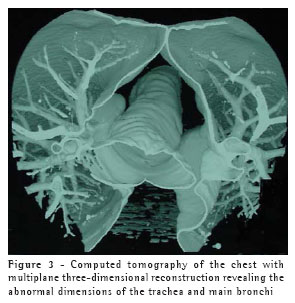

A 40-year-old black male patient was referred to the pulmonology clinic due to fatigue upon exertion and persistent dry cough three weeks after having been discharged from the hospital, where he had been admitted for treatment of pneumonia. The patient had presented, 40 days prior, a sudden onset of fever, a productive cough with a limited amount of hemoptysis, and dyspnea. He was diagnosed with pneumonia and was hospitalized, receiving intravenous cefazolin for seven days. He presented favorable evolution. The patient also reported having experienced three previous episodes of pneumonia, the first at the age of 22. The chest X-ray performed at the time of the evaluation revealed discrete areas of consolidation, of residual aspect, in the middle lobe, as well as a significant increase in the diameter of the trachea and of the main bronchi.

The patient underwent empirical treatment with a bronchodilator for two weeks, with no improvement, and then returned for a reevaluation. The cough had worsened, becoming productive. The chest X-ray taken at that time revealed new areas of consolidation in both lower lobes and in the middle lobe. There was no alteration in the vital signs, and the patient presented good general status. A ten-day course of oral erythromycin was prescribed. Over the first three days, the cough and fatigue lessened. By the end of the ten-day period, the cough had almost completely disappeared.

This treatment continued for four weeks, by which time the symptoms had been completely resolved. At that point, the patient was submitted to a computed tomography scan of the chest, which revealed that the areas of consolidation, although smaller in size, persisted in both lower lobes, and confirmed the abnormal widening of the trachea and main bronchi (Figures 1, 2 and 3). In the lower lobes, there was bilateral cylindrical bronchiectasis, which is consistent with a diagnosis of congenital tracheobronchomegaly, or Mounier-Kuhn syndrome. Pulmonary function tests revealed an increase in total lung capacity (123% of predicted) and residual volume (160% of predicted), with no other alterations. Currently, the patient remains asymptomatic, and has daily respiratory therapy sessions. Annual immunization against influenza has been recommended.

Diagnosis can usually be made by measuring the tracheal diameter, using only data from chest X-rays, in which the trachea can seen in profile and thus the diameter determined. Computed tomography of the chest, however, makes this measurement more precise. The limits are 3 cm for the transverse diameter of the trachea, and 2.4 cm and 2.3 cm for the transverse diameters of the main right and left bronchi, respectively.